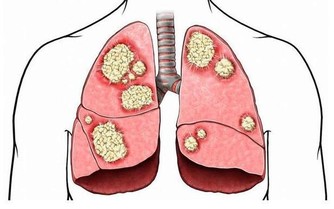

當我們談到有關女性的癌症類型時,你必然會提起乳腺癌,因為這是女性發病率最高的癌症。然而與此同時,大家一定不要忘了卵巢癌,這也是一名同樣危險的殺手,發病率也相當高。

而且,卵巢上皮癌死亡率,佔各類婦科腫瘤的首位。其死亡率如此之高,重要原因是很難早期發現。我們身邊會有一些女性知道對乳房進行自檢,卻不知道關注卵巢癌的跡象。

那麼,卵巢癌都有哪些比較典型的症狀呢?很遺憾,並沒有那樣一個確定的信號,讓我們一看到就知道這個人患了卵巢癌。但好消息是,如果一名女性罹患卵巢癌,會有一個症狀比較突出,那就是“尿頻”,然而根據英國慈善機構的調查結果,大約只有百分之一的人知道經常需要排尿是卵巢癌的症狀。